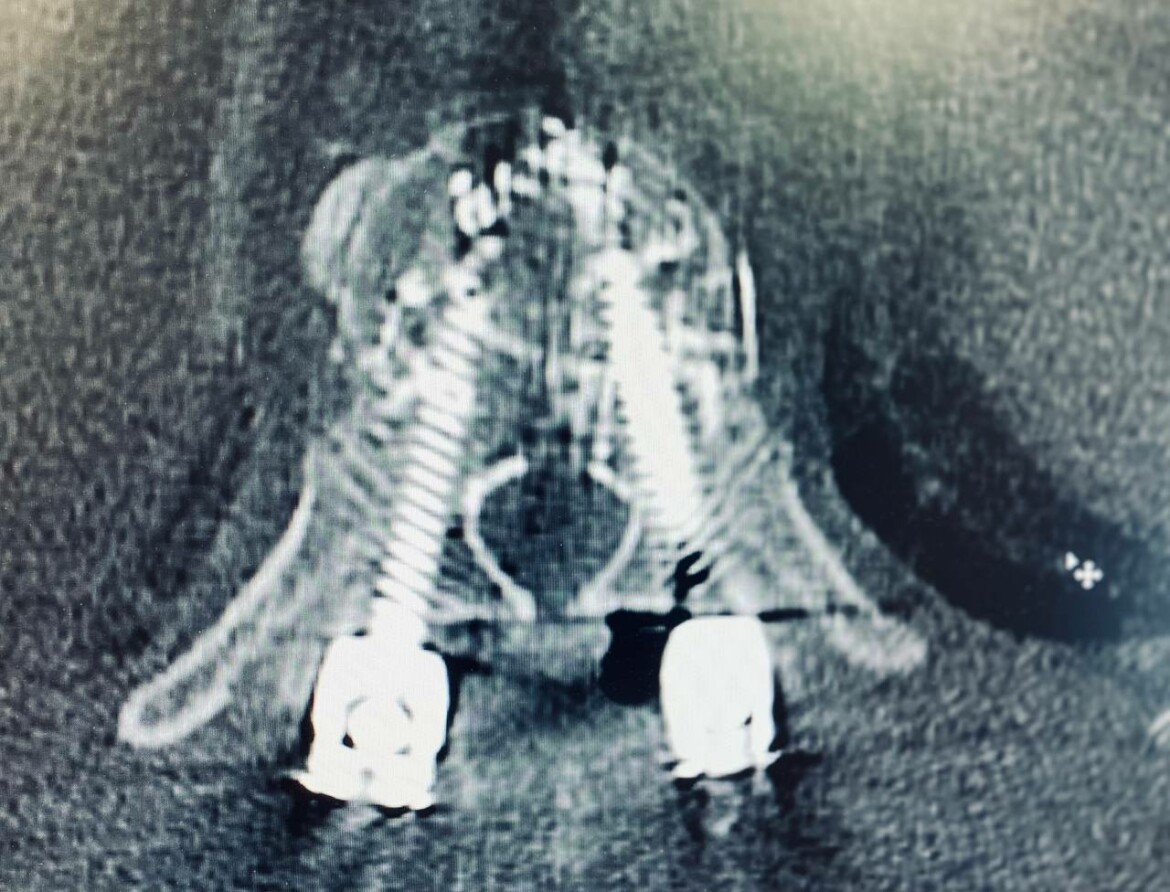

Операцию врачи проводили современной методикой под контролем рентгена. Хирурги установили восемь винтов из титана в позвоночник, скрепив конструкцию специальным цементом для костей.

«При установке фенистрированных винтов нет права на ошибку. Нужно четко попасть в тело позвонка через ножку, сохранив все стенки, чтобы цемент не попал в позвоночный канал и близлежащие сосуды», – рассказал нейрохирург БСМП Ильфат Фатхутдинов.